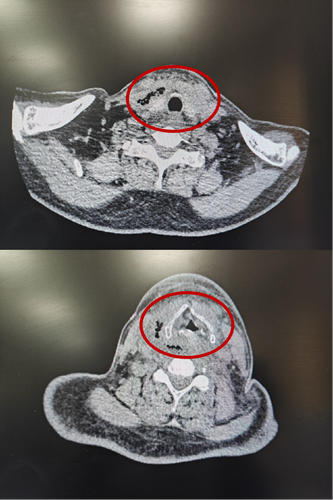

患者乙CT示:颈部咽后间隙—右侧咽旁间隙—右侧颈动脉间隙脓肿